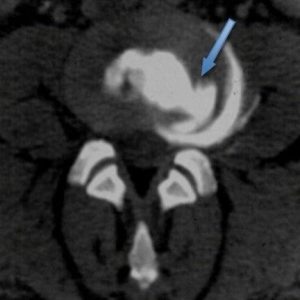

Hérnia de Disco L5 / S1 no canal vertebral no lado esquerdo

Esta patologia representa cerca de 80% das causas de dor lombar em pacientes jovens (20-50 anos), em particular entre trabalhadores com elevada carga física.